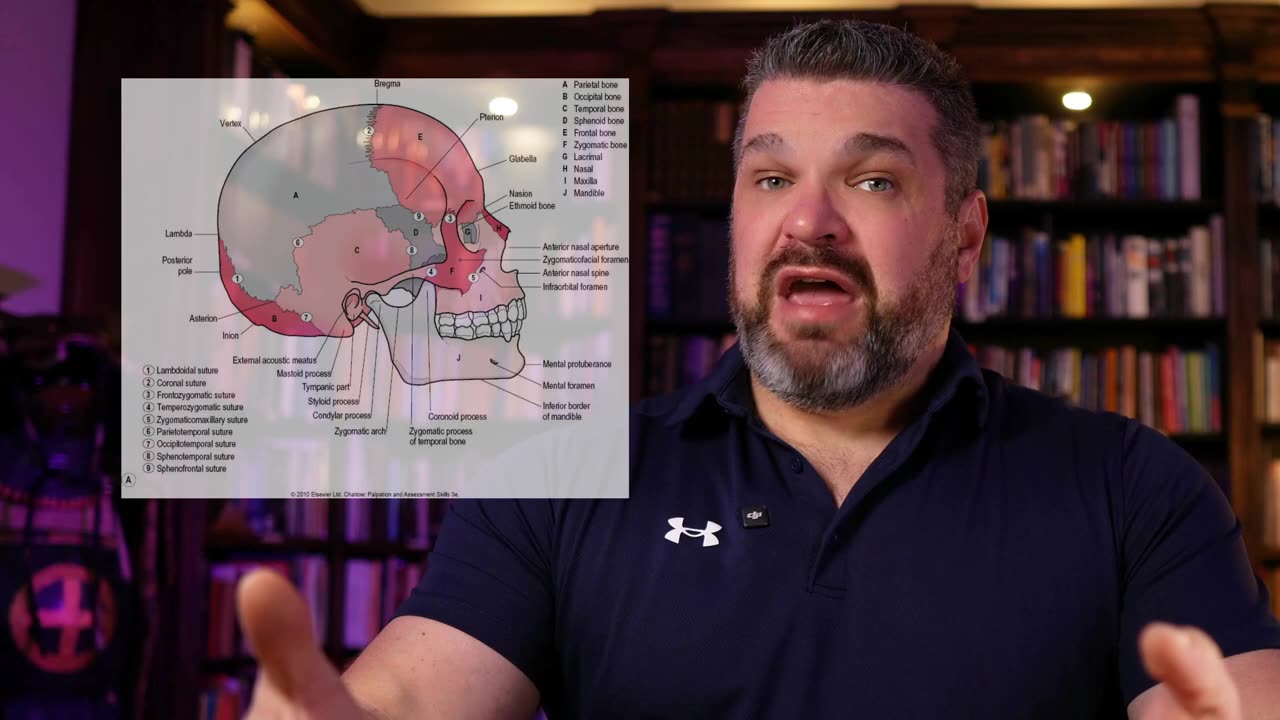

These symptoms are screaming that a BRAIN ANEURYSM is app...